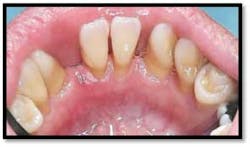

UL/LL reflected in a mirror and UL/LL radiograph

Tissue is light pink, tight and firm. All pockets are 1-3mm, no BOP

Tissue is light pink, tight and firm. Pockets 1-3mm no BOP